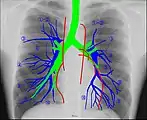

Human chest radiographic anatomy. Human chest radiographic anatomy.

Radioanatomy (x-ray anatomy) is anatomy discipline which involves the study of anatomy through the use of radiographic films.[1] The x-ray film represents two-dimensional image of a three-dimensional object due to the summary projection of different anatomical structures onto a planar surface.